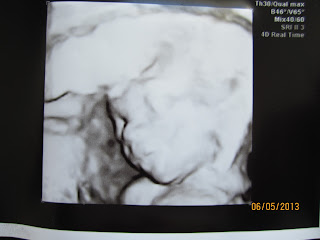

Rakenneultra rv 20+5

Myttysellä on aivan samanlaiset kasvonpiirteet kuin isoveljellään <3

Ultran mukaan kaikki on kunnossa. Ultraaja joutui pitkään hakemaan hyviä kuvakulmia, kun tyyppi bailasi niin ankarasti ympäri yksiötään. Välillä hän piti käsiä naaman edessä, välillä taas käsi oli suussa tai haarovälissä. Saatiin kuitenkin nämä pari hyvää 4D-kasvokuvaa, jotka tosin näyttävät vähän suttuisilta kameralla kuvattuna.

Painoa on 367g tällä hetkellä ja mitat vastaavat viikkoja. Istukka sijaitsee etuseinässä... Ilmankos noita liikkeitä ei ole tuntunut ihan niin hyvin mitä Pikkukarhusta. On niin helpottunut olo, kun kaikki on ainakin näillä näkymin kunnossa.